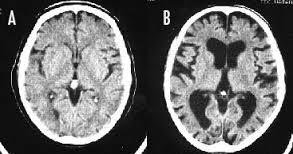

喫煙をすると、頭が悪くなるのは本当です。 長期の喫煙により、大脳皮質が薄くなり、認知機能が低下してしまうのです。 画像左(A)は正常な脳、右(B)は喫煙者の脳です。 正常な脳と比べて、喫煙者の脳は、萎縮して隙間だらけになってしまっています。 喫煙をやめても、元の状態に回復するまで、数十年はかかるそうです。

--- 「喫煙者の脳」やはり異変が起きていた(石田雅彦) - Yahoo!ニュース ---

タバコを吸うと脳がすっきりするのは真っ赤な嘘だ。研究によれば喫煙者の脳では明らかに異常が起きている。認知機能も低下し、大脳皮質が元に戻るのには25年もかかる。一刻も早くタバコなど止めたほうがいい。